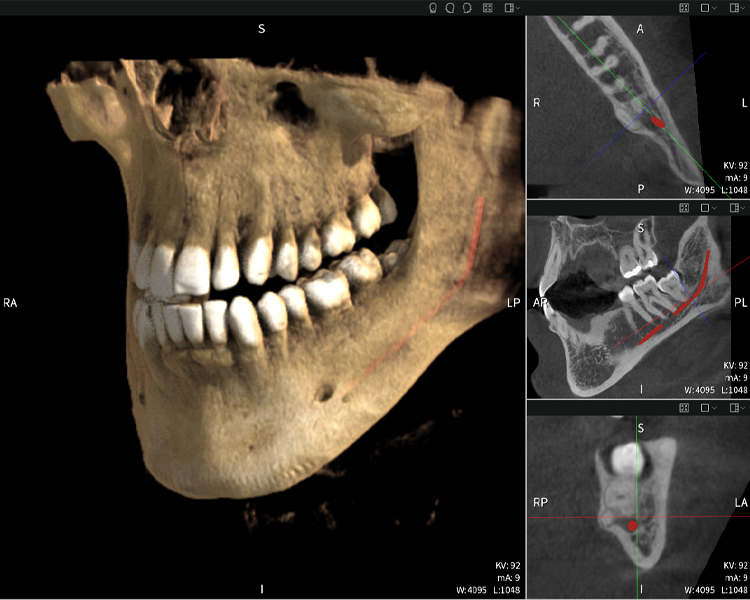

Figures b–d show various views of a 3D reconstruction of the mandible, providing a comprehensive overview of the mandibular anatomy, the position of the nerves in relation to the teeth, and allowing assessment of tooth symmetry and alignment.

Figure c: Imaging results of Seethrough Max, in front of a black background.

Figure c

Figure d shows the previously treated tooth 48, with its crown removed, and its roots left in proximity to the nerve, illustrating the high risk of nerve damage.